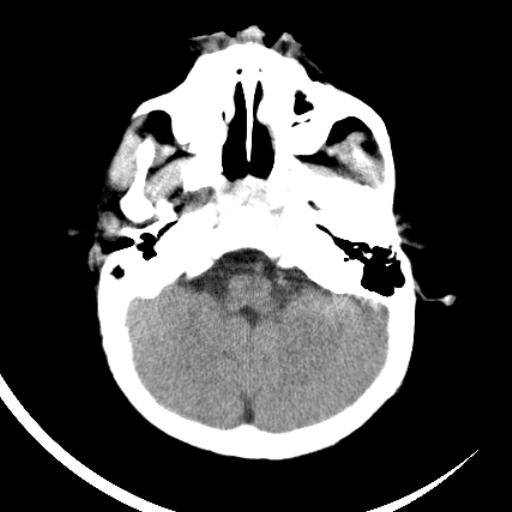

双侧脑室前后角周围白质片状低密度影,双侧侧脑室旁、双顶叶皮层及皮层下多个小原点状钙化灶,不除外torch感染。右顶叶脑回似乎较对侧大,建议mri检查以除外脑发育异常。

考虑:1、巨脑回畸形(皮质明显增厚+脑回明显增宽+白质减少)。

2、torch综合征(室管膜下钙化+白质内及皮髓质交界处多发钙化)。